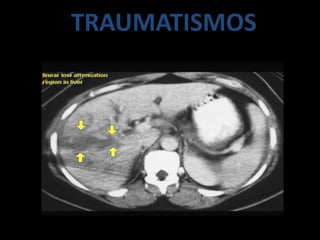

TRAUMATISMOS

• LA TOMOGRAFIA TIENE EL MAYOR EFECTO.

• DETECCION EXELENTE PARA PACIENTES

POLITRAUMATIZADOS HEMODINAMICAMENTE

ESTABLE

• VALORACIÒN INICIAL.

• VER LOCALZACIÒN Y EXTENSIÒN

• LAS LESIONES TRAUMATICAS PUEDEN SER :

– CONTUSIONES

– DESGARROS

– HEMATOMAS

– ROTURAS

– LACERACIONES

• EN TC :

CONTUSION SIN ROTURA SE MANIFIESTA COMO

IMAGEN HIPODENSA EN CONTRASTADA ESTO

PUEDE SER POR EDEMAS Y HEMORRAGIAS

MICROSCÒPICAS

DESGARRO HEPATICO

TRAUMATISMO: INJURIA HEPATICA